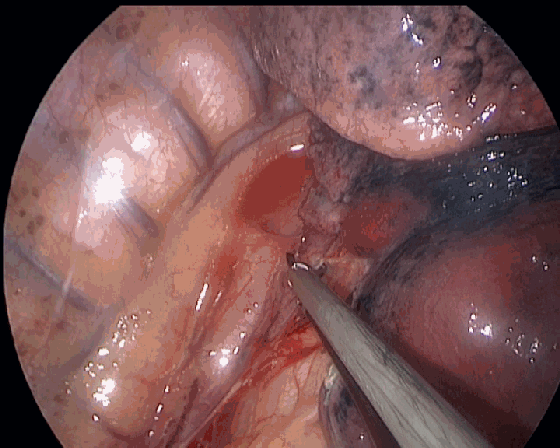

超声刀正在游离切割下肺韧带,加持了钝性分离的撕扯力量,让下肺韧带的游离速度更快。

超声刀正在打开纵隔胸膜,加持张力以后,组织间隙更清楚,切割速度也更快,类似于电钩挑起的道理。